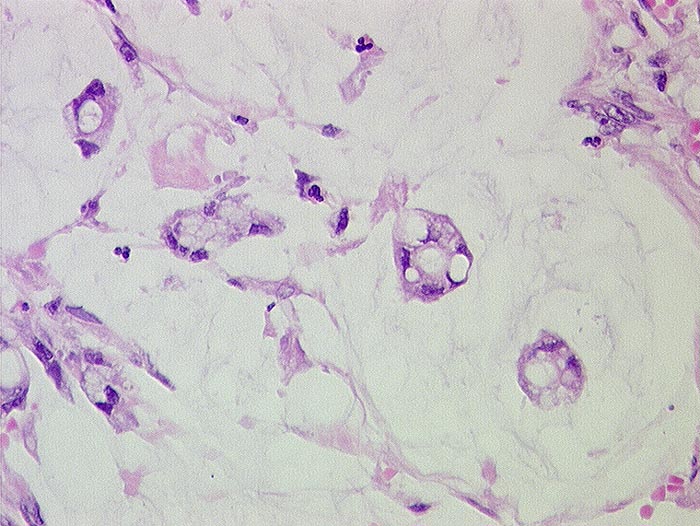

PathoPic ID 328 - Muzinöses Adenokarzinom

Muzinöses Adenokarzinom

maligner Tumor

Appendix vermiformis

Darm, Anus

Kleine Tumorzellgruppen schwimmen in Schleimseen.

pT4, pM1 (Peritonealkarzinose)

V.a. Ovarialkarzinom

Histologie